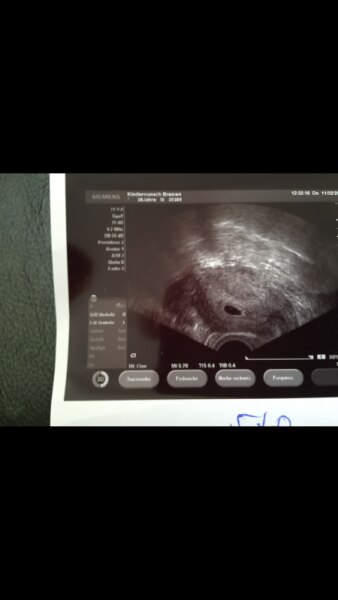

Huhu! Ich hab hier ein Bild von 5+0. Man sieht es so leider schlecht, aber oben links in der Fruchthöhle war schon ein kleiner Punkt erkennbar. Aber bitte denk dran, dass jede Schwangerschaft anders verläuft....nicht, dass dich das verunsichert. Liebe Grüße

Bild zu